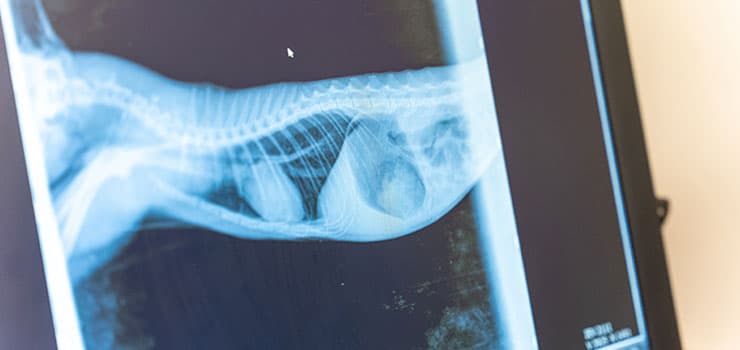

Diagnostic Imaging

• Digital X-rays reveal bones, joints, lungs, and internal structures.

• Ultrasound shows soft tissues and organs in motion—great for abdominal and heart evaluations.

Our honest answer? It depends. Sometimes these diagnostics give us a clear “aha” moment right away. Other times, ultrasounds and X-rays help us narrow down what could be happening to your pet to one or two issues instead of our team guessing at many issues. We’ll always talk through why we suggest diagnostics in your pet’s case, and how they’ll help us arrive at an answer or find the best next step forward.